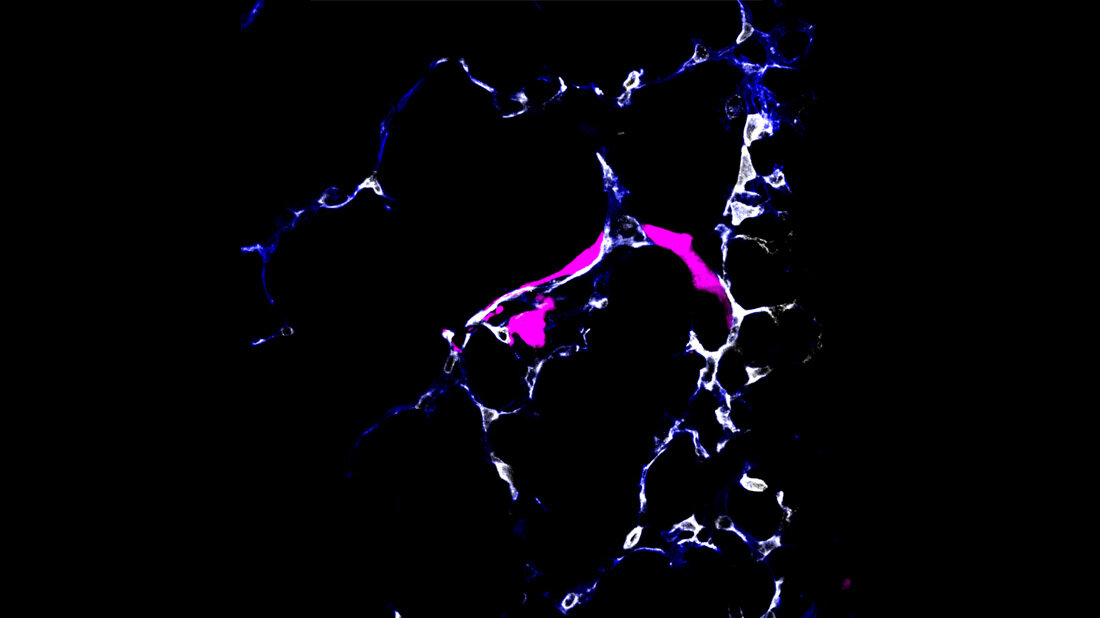

Um sich im Körper zu verbreiten, nutzen Krebszellen die Blut- oder Lymphbahnen. Wissenschaftler im Deutschen Krebsforschungszentrum (DKFZ) und in der Universität Heidelberg haben nun ein Verfahren entwickelt, um bei Mäusen das Verhalten wandernder Krebszellen unmittelbar bei Ankunft im metastatischen Organ – in diesem Fall der Lunge – zu beobachten. Dabei entdeckte das Team um die beiden Erstautoren Moritz Jakab und Ki Hong Lee, dass manche Tumorzellen, sobald sie im Zielorgan angekommen sind, aus dem Blutgefäß austreten und in einen Ruhezustand fallen. Andere Krebszellen dagegen fangen direkt im Blutgefäß an, sich zu teilen und zur Metastase auszuwachsen.

Diese Entscheidung wird von den Endothelzellen gesteuert, die alle Blutgefäße von innen auskleiden. Sie schütten Faktoren des Wnt-Signalwegs aus, die den Austritt der Tumorzellen aus dem Blutgefäß fördern und damit den Ruhezustand einleiten. Schalteten die Forscher die Wnt-Faktoren aus, kam es nicht mehr zur Latenz. „An diesem Punkt stellte sich uns die Frage: Warum bilden einige Krebszellen sofort eine Metastase, wohingegen andere in eine Art Schlaf verfallen?“, sagt Moritz Jakab. Genetisch unterschieden sich die ruhenden und die metastasenbildenden Krebszellen nicht, auch nicht in vielen anderen molekularen Aspekten.